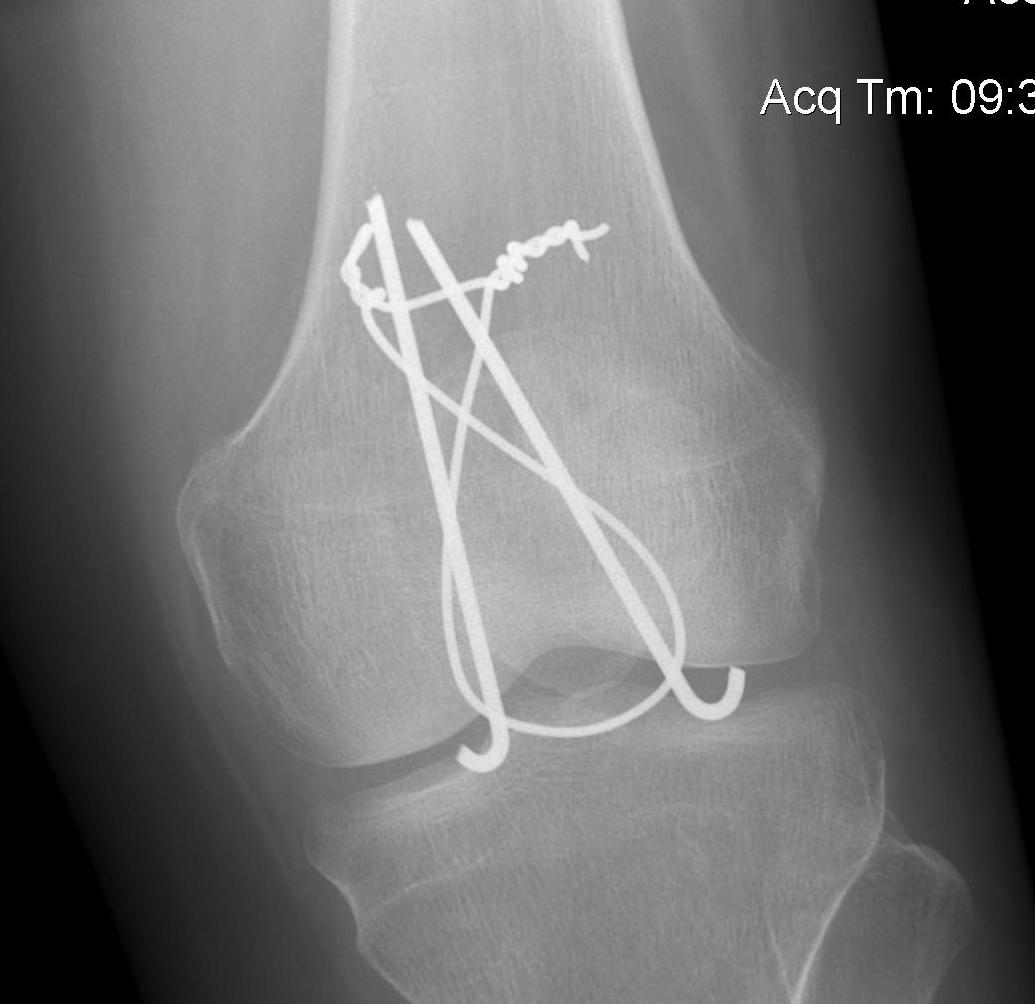

1. TBW

2. Cerclage wire +/- ORIF

- stellate fractures